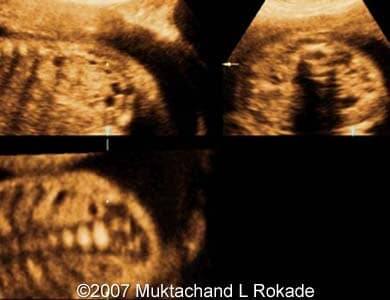

The following images show a case of the unilateral multicystic dysplastic kidney disease detected at 24 weeks of pregnancy.

Images 1, 2: Parasagittal scans of the right fetal kidney with the multicystic kidney disease detected at 24 weeks of pregnancy.

Image 3: Multiplanar view showing the right multicystic kidney disease of the 24 weeks old fetus.